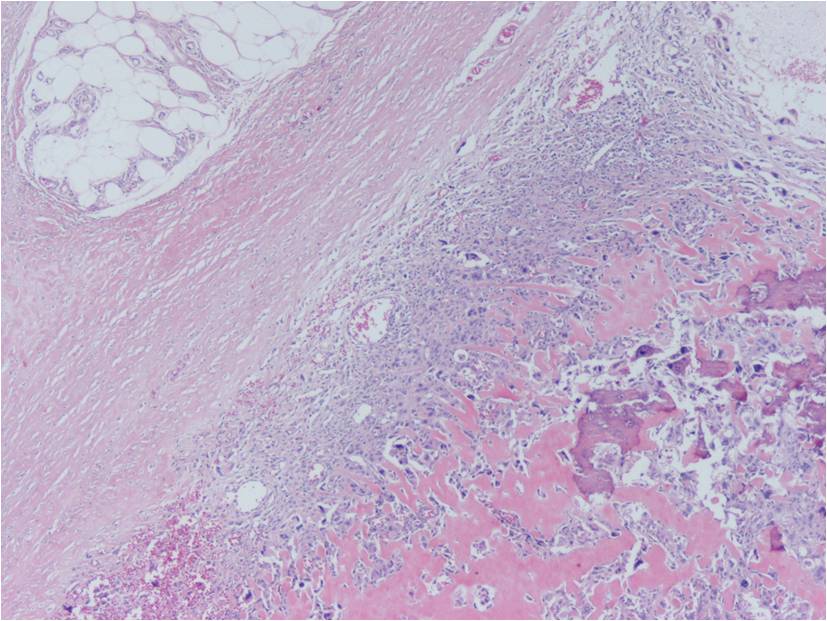

Extraskeletal osteosarcoma is generally a high-grade malignancy, similar to a high grade conventional intraosseous osteosarcoma. Microscopically, tumors usually have an infiltrative margin with occasional satellite nodules; however, on gross inspection they appear well defined. Tumor cells produce a variable amount of osteoid and bone (Fig. 8-10). Necrosis and hemorrhage are common. Five subtypes have been described similar to conventional osteosarcoma of bone: osteoblastic; chondroblastic; fibroblastic; telangiectatic; and small cell.

Fig. 8-10: Microscopic Pathology. Low (Fig. 8), intermediate (Fig. 9) and high (Fig. 10) power magnification H&E slides. Osteoid and bone formation produced by tumor cells, without interposition of cartilage. Tumor cells are crowded, disorganized, pleomorphic and darkly stained. There are mitotic figures.